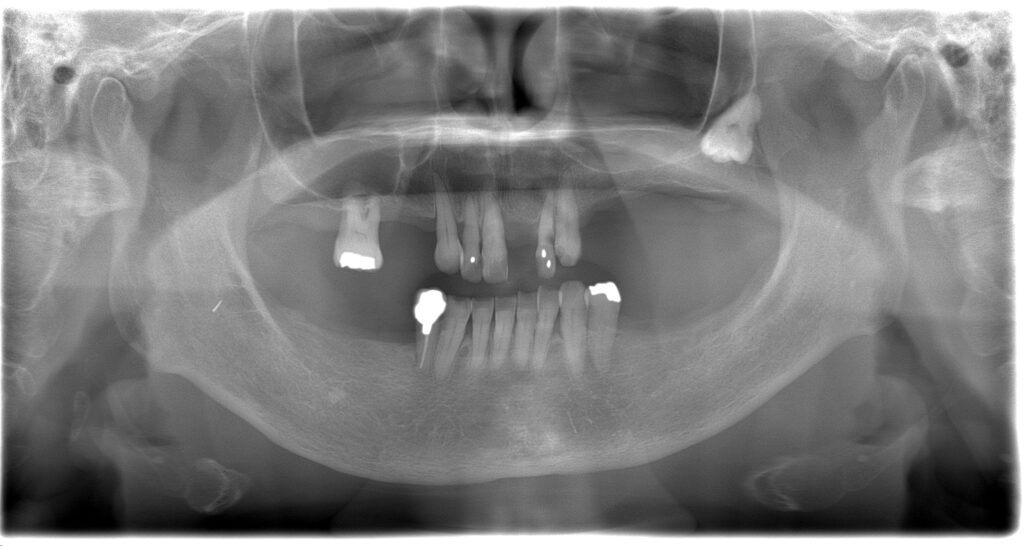

BEFORE

AFTER

主訴

全体的に見た目を綺麗にしたい。奥歯でしっかり噛みたい。

診断名・主な症状

臼歯部欠損

年齢

65歳

治療内容

インプラント埋入(左下5・6,右下5・6,左上4・6)

サイナスリフト(左上4・6)

ジルコニアBr(右上6−左上3)

E –MAX CAD(右下4)

セラミックインレー(左下4)

治療期間/

通院回数

約1.5年/約20回

費用

インプラント治療 約2,000,000円

その他被せ物治療など 約1,000,000円

合計 約3,000,000円

*いずれも税込